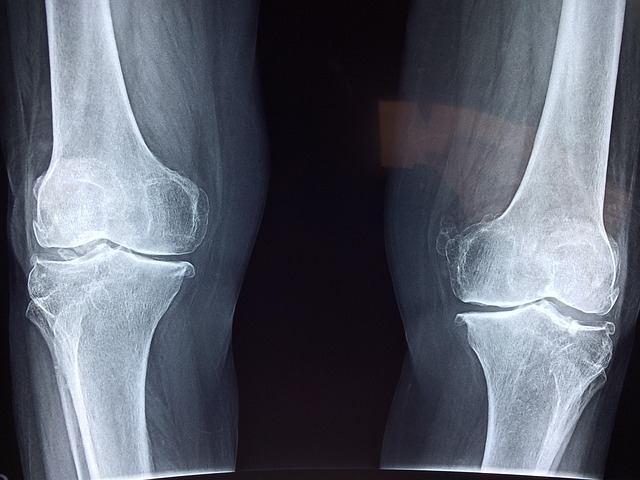

골밀도 검진 방법과 진단

골밀도는 뼈의 강도를 나타내는 지표로, 골밀도 검사를 통해 측정할 수 있습니다. 이중 에너지 X-레이 흡수계측법(DXA 스캔)이 가장 널리 사용되는 검사 방법으로, 척추와 고관절 부위의 골밀도를 측정합니다. 검사 결과는 T-점수로 표현되며, T-점수가 -2.5 이하일 경우 골다공증으로 진단됩니다.

골다공증은 뼈의 강도가 약해져 쉽게 골절되는 질환으로, 특히 고령자에게서 흔하게 발생합니다. 골다공증의 위험 요인으로는 유전적 요인, 낮은 체질량지수(BMI), 흡연, 과도한 음주 등이 있으며, 이러한 요인들을 관리하는 것이 예방에 중요합니다.